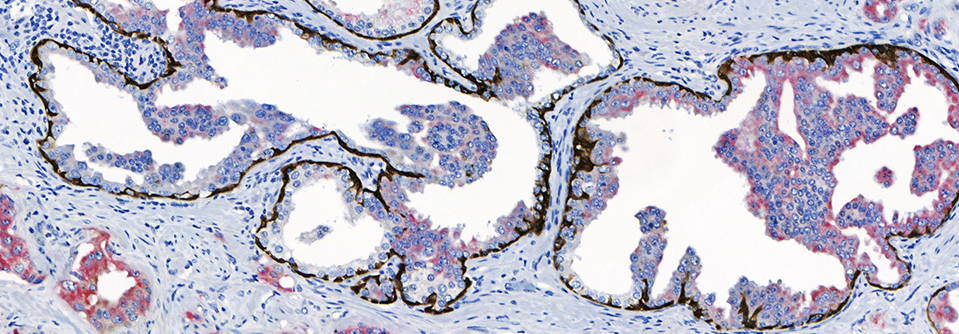

• Sharp & Well-Defined Staining

NeoPATH Pro sets a new standard in automated advanced staining for IHC, ISH, and FISH. Designed to meet your laboratory’s current staining needs while adapting to future demands, this advanced staining platform delivers high-capacity throughput, optimized reagents, and intuitive automation. Innovative features such as independent slide positions, integrated slide scanning, and Al assisted error prevention streamline workflows and enhance diagnostic confidence.

IHC, ISH, FISH |